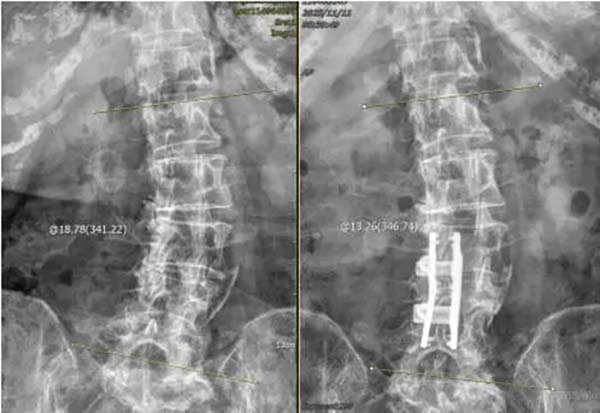

▲术后侧弯亦得到纠正

手术当日,脊柱外科(骨四科)团队为患者施行手术。术中团队操作精细,全程密切配合,仅1小时30分钟手术顺利结束。术后患者恢复良好,腰腿痛明显好转。术后三天患者即可下地行走,术前存在的下肢疼痛、麻木及双腿沉重感均得到明显改善。